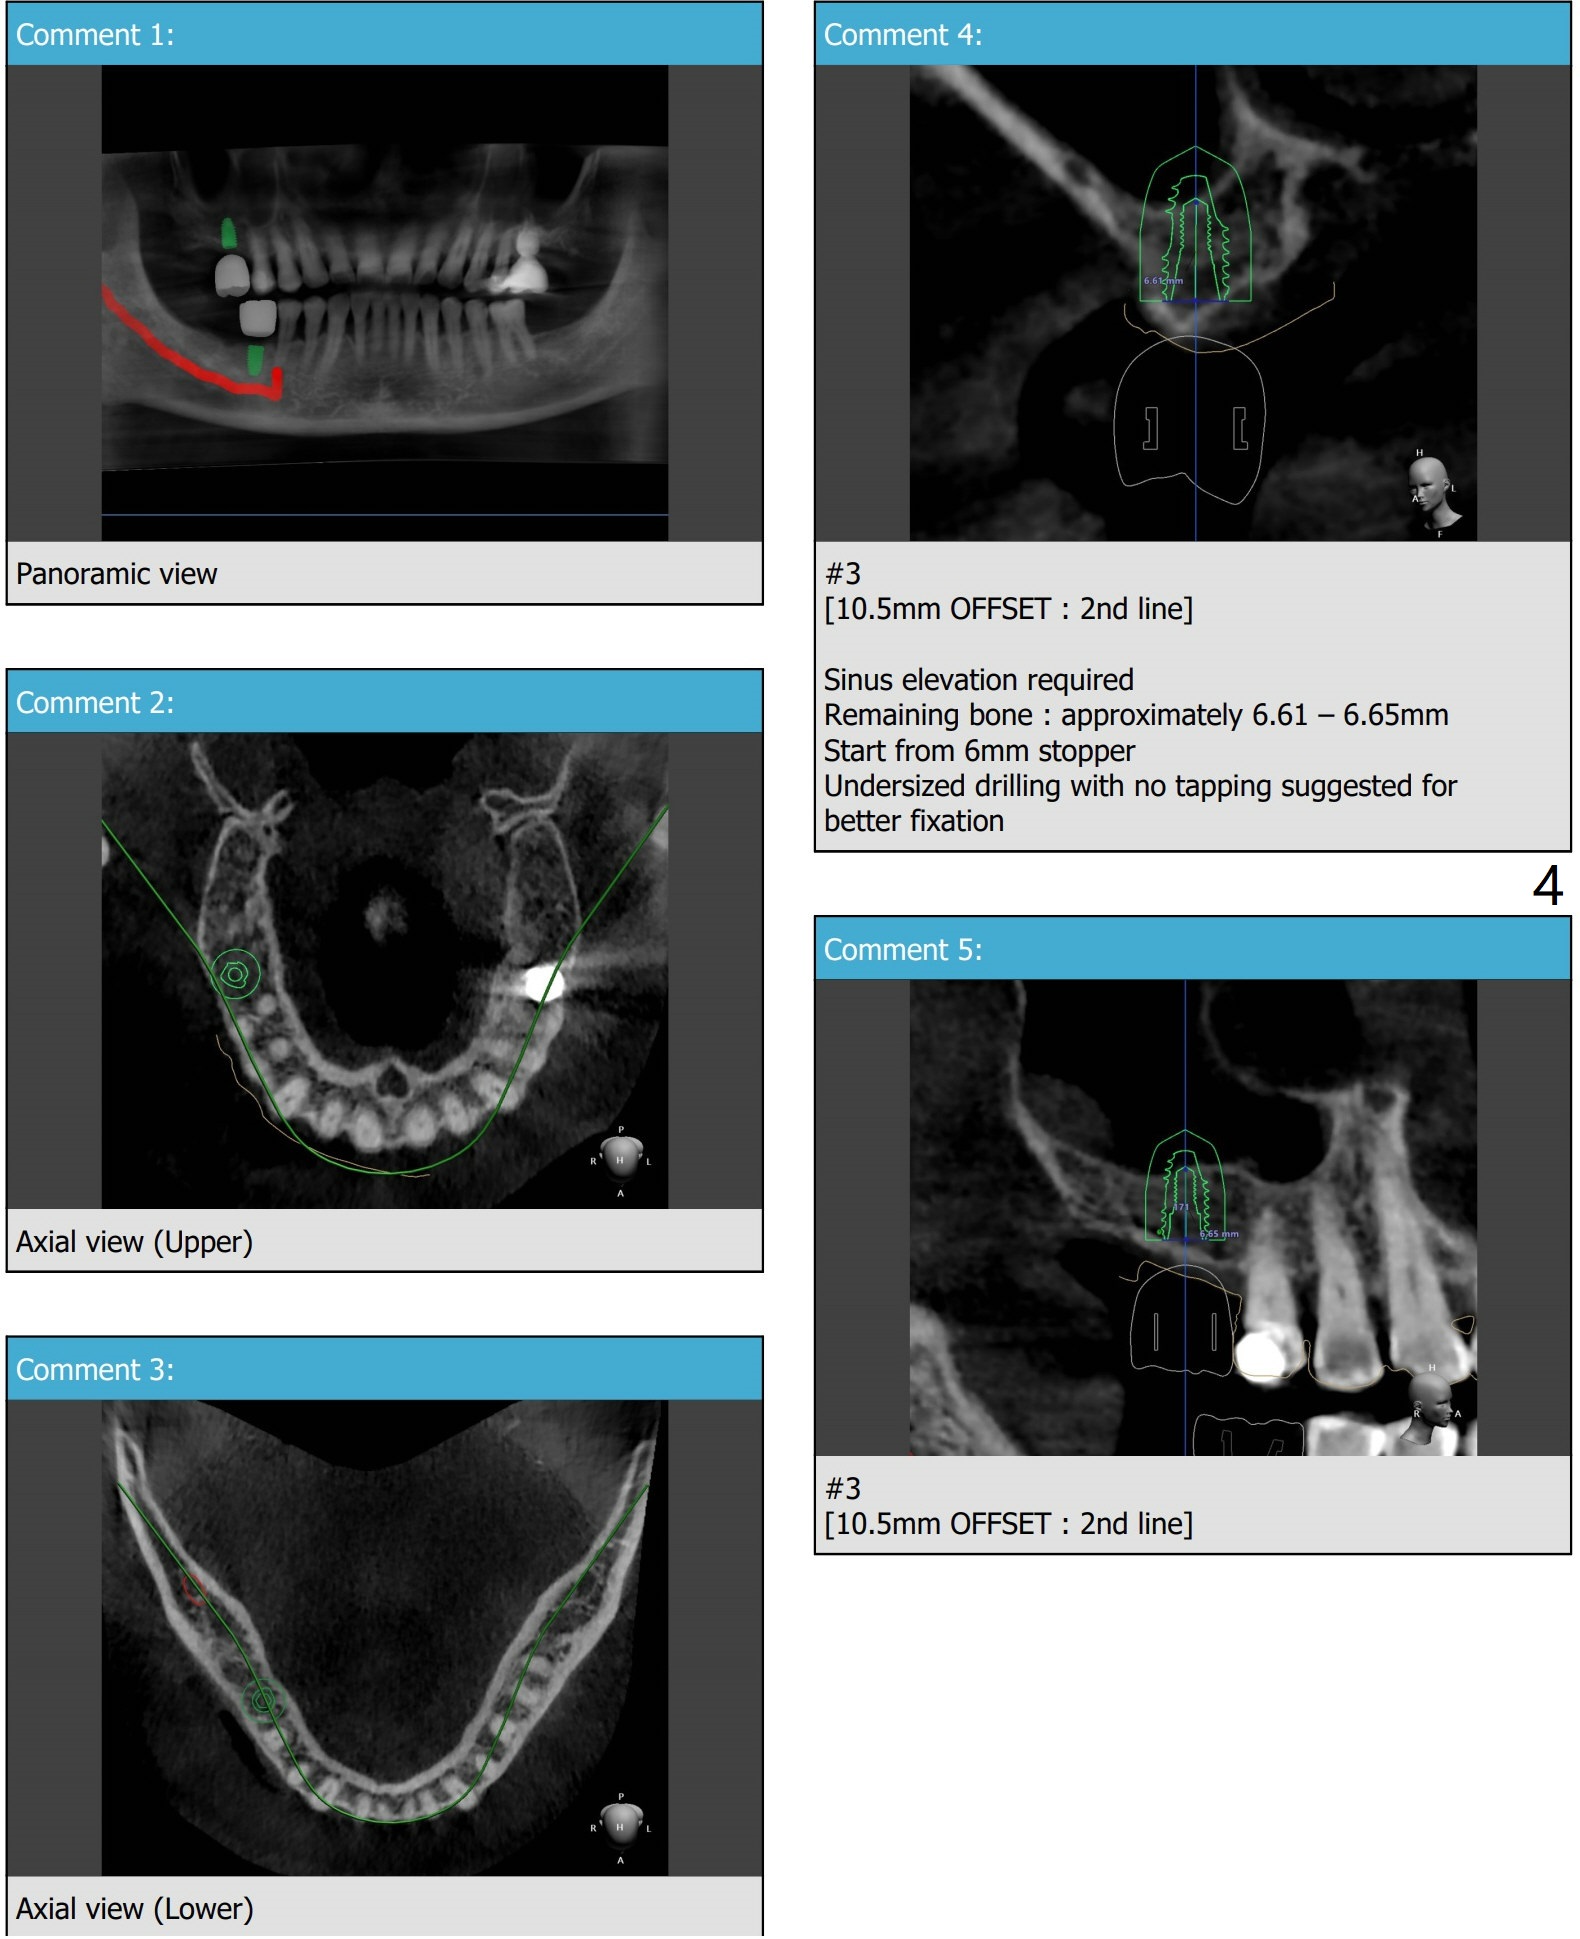

66岁男缺失右上,右下第一磨牙许久,需要上颌窦提升。Because of sinus lift, make a little sticky bone, considering autogenous bone from #30 and 3 osteotomy sites. Tube x1.